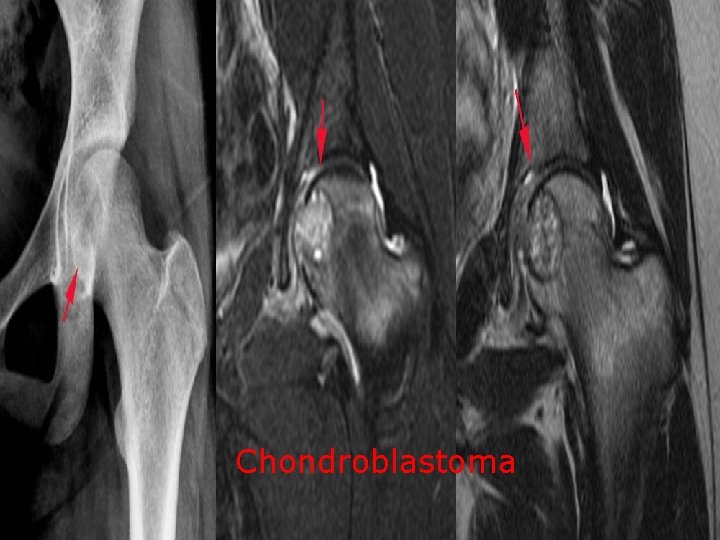

Adamantinoma

Concerning Malignant bone lesion: a. Chordoma os most common in the thoracolumbar spine b. (X ) 90% in basisphenoid and sacrum Fibrosarcoma is the commonest tumour 2 ry to paget’s disease c. (√ ) Adamantinoma occursin the tibia in over 90% of cases (√ ) d. Angiosarcoma has a soap bubble appearance at radiography e. (√) Chondroblastoma are typically found in the diaphysis (X ) they are epiphyseal lesions

Chondroblastoma